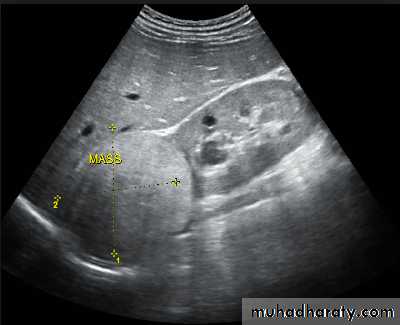

Renal ultrasound is a simple noninvasive examination .The kidney is bean shaped and has bright central echoes because of the fat surrounding the collecting system.

Ultrasound is typically ordered to exclude , stones , hydronephrosis or to evaluate renal size or suspected renal cysts .

Normal renal ultrasound.

A longitudinal view of the right kidney was obtained by passing the sound beam through the right lobe of the liver. The kidney is seen behind this, outlined by the markers. The central bright echoes in the kidney are due to fat around the collecting system.